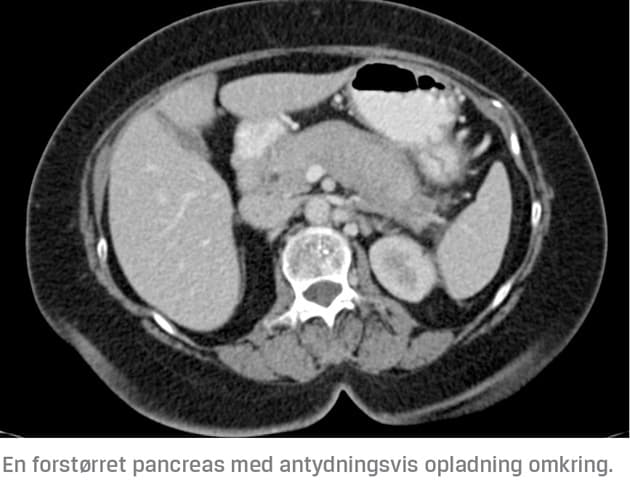

Det er hyppigst fund ved MR-skanning eller CT, der leder til mistanke om AIP. De to AIP-typer kan ikke adskilles ved skanning. En fokalt eller diffust forstørret pancreas, specielt med en kapsellignende forandring omkring sig, uden dilatation af ductus pancreaticus bør rejse mistanke om AIP [1]. Diffus forstørrelse af hele pankreas findes hos 30-40% af patienterne [4-6, 12], fokal forstørrelse hos 35-75% [4-6, 12], kapsellignende forandring hos 30-48% [4, 12] og forsinket opladning hos ~ 90% [12]. Ovennævnte fund kan gøres ved både MR-skanning og CT, men specielt MR-skanningens T1- og T2-vægtede billeder er vigtige ved diagnostikken af AIP [13]. Forandringer, der er forenelige med AIP, er næsten altid hypointense på T1-vægtede billeder og hyperintense på T2-vægtede billeder.